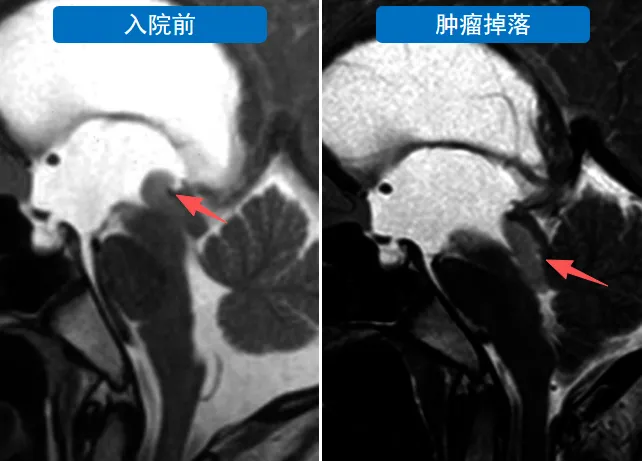

入院当日办理手续过程中,患儿突发意识丧失晕倒。医疗团队立即进行急诊MRI检查,施罗德教授评估影像后确认需行急诊手术干预。病情急剧恶化原因为带蒂肿瘤移动至中脑导水管造成完全性阻塞,脑脊液循环通路中断导致急性颅内压升高。

在患儿昏迷状态下,医疗团队实施神经内镜手术。手术采用右侧额头部直径2cm骨孔入路,避免传统开颅手术创伤。内镜下可见肿瘤完全阻塞导水管入口,肿瘤通过细蒂与脑组织相连。施罗德教授实施肿瘤完整切除手术,重建脑脊液循环通路。